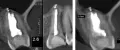

Начал разрушаться зуб, верхняя левая 6. Обратился к стоматологу. Сделали рентген, высверлили каналы, в общем, за несколько походов мне его нарастили.

Без нареканий ходил четыре года, недавно почувствовал боль при надавливании (и только в определенных направлениях).

Чувствуется, что внутри незначительное воспаление. Боль тупая, при надавливании - острая, простреливающая, при этом болит не всегда. Ближайшие две недели физически не смогу посетить стоматологию.

Не имея данных рентгенологического исследования, могу предположить хроническое воспаление на корнях (периодонтит), либо патологический зубодесневой карман.